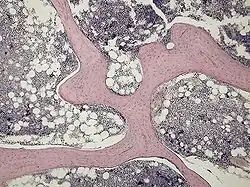

Spongy or Trabecular Bone

Trabecular bone appears in vertebrae and the metaphyses (ends) of long bones.